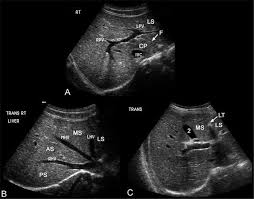

What that something is well that depends on the size solidity and location of the spots. Heifer calf equine ultrasound. The condition affects one in 500 live born babies and is the most common abnormality detected on prenatal ultrasound scans accounting for up to two thirds.

A regular ultrasound shows shades of black and white to ident. As i soon learned all too well hydronephrosis is a condition that involves a backflow of urine in the kidney because of an obstruction. The condition affects one in 500 live born babies and is the most common abnormality detected on prenatal ultrasound scans accounting for up to two thirds. I m 15 years old and relatively healthy but for almost a year now i ve been experiencing severe abdominal pain.